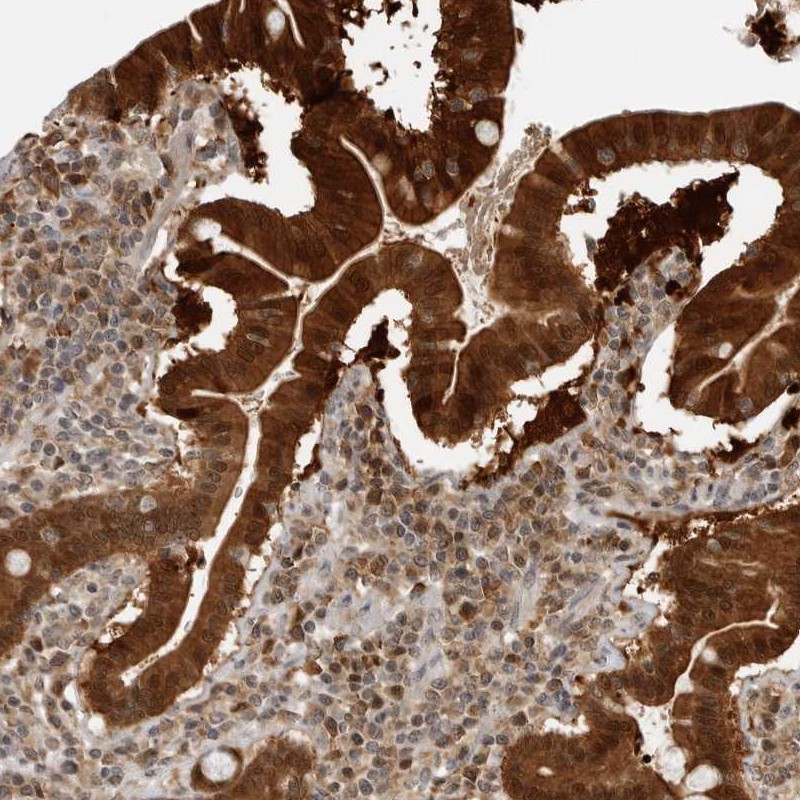

Immunohistochemical staining of human duodenum shows strong cytoplasmic and nuclear positivity in glandular cells.